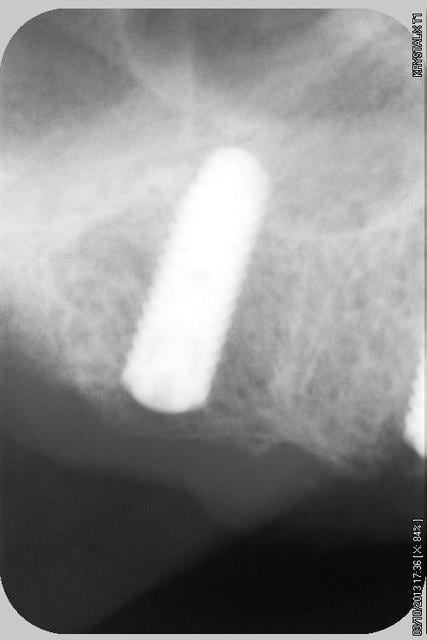

quelques radios.

oui, bien sur ce sont des Tatum D1 en bas et D4 en haut